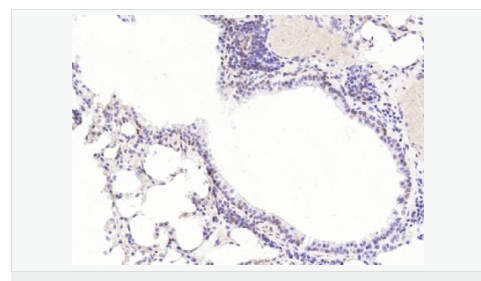

| 產(chǎn)品應(yīng)用 | WB=1:1000-2000 ELISA=1:1000-5000 IHC-P=1:100-500 IHC-F=1:100-500 Flow-Cyt=1ug/Test ICC=1:100-500 IF=1:100-500 (石蠟切片需做抗原修復(fù)) not yet tested in other applications. optimal dilutions/concentrations should be determined by the end user.  |

| 細(xì)胞定位 | 細(xì)胞核 細(xì)胞漿 |